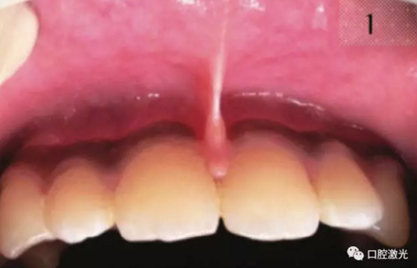

術(shù)前

一般而言,正常的唇系帶應(yīng)該在門牙齦緣上方至少有4mm間隙,并且不能影響或限制嘴唇的正常移動(dòng)。如果發(fā)生唇系帶過(guò)低,則會(huì)有以下影響:

擴(kuò)大牙間隙:由于系帶中纖維組織下移至門牙中間位置,從而導(dǎo)致牙齒中間形成較大的縫隙,影響美觀。